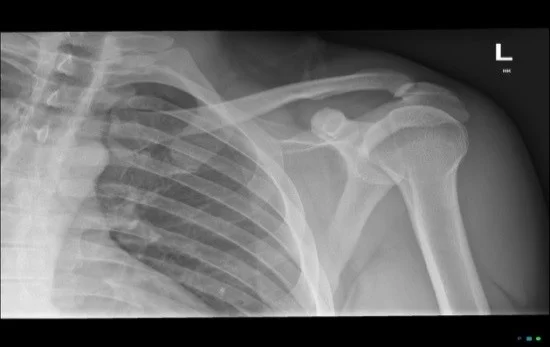

In normal configuration, the inferior cortices of the clavicle and acromion are in alignment (Figure 3). Additionally, the coracoclavicular distance is normally less than 13 mm or there is a less than 5 mm difference between the left and right coracoclavicular distances. (1; 3) Figure 4 depicts normal alignment of the inferior cortices of the acromion in red and highlights the coracoclavicular distance in white.

If acromioclavicular joint injury is suspected, three-view radiographs of the shoulder (anteroposterior view, scapular-Y view, axillary view) and a Zanca view (a specialized anteroposterior radiograph which removes the scapula from behind the joint) allow for identification of vertical displacement of the clavicle and for anteroposterior displacement of the clavicle. (2) AP comparison views of both AC joints can also be helpful in diagnosis of AC joint injury.